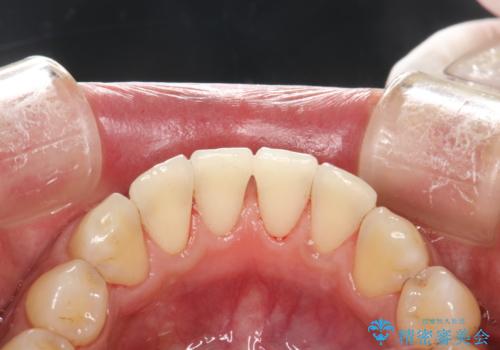

- 全体的な着色(ステイン)、黄ばみが気になるとのことで、来院されました。着色(ステイン)などの付着量が多かったためPMTCの60分コースを行いました。

PMTCを行うと、着色(ステイン)や歯石などを除去することができます。

PMTCは、歯科医院にて専門的な機械・材料を使用して行う専用クリーニングです。着色(ステイン)や歯石を取り除くことで、ご自身の本来の歯の色となります。また、施術後にはスッキリとした爽快感あ得られたり、歯の舌ざわりがツルツルになり気持ちがいいです。